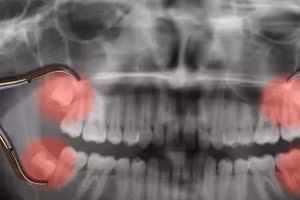

GD&TĐ - Nhổ răng khôn gần như đã là một việc mà phần lớn thanh thiếu niên từng trải qua. Vậy tại sao những chiếc răng kì quái này lại không mọc từ thời thơ ấu của chúng ta như những chiếc răng khác?

Những cơn đau nhức dai dẳng khi mọc răng khôn luôn là nỗi ám ảnh với rất nhiều người. Nếu bạn đang trong tình trạng này có thể tham khảo các cách dưới đây.